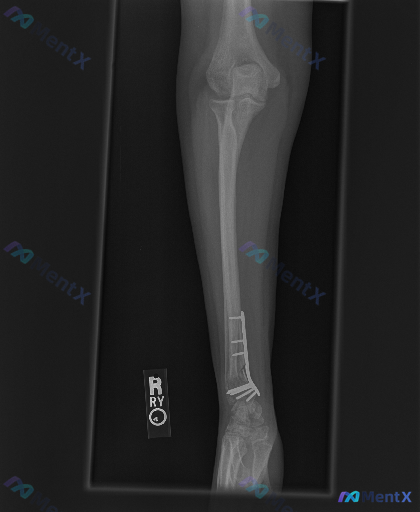

右侧桡骨远端内固定术后复查影像,你会怎么评估当前状态?

整理到一个骨科术后复查的影像病例,先把核心资料整理出来给大家看看: - 背景:成年患者,右侧桡骨远端骨折内固定术后复查 - 影像类型:前臂X光正位片 - 关键影像表现: 1. 右侧桡骨远端可见接骨板及多枚螺钉固定,位置与骨骼结构基本匹配 2. 桡骨远端可见陈旧性骨折痕迹,骨折断端有骨痂形成 3. 桡...